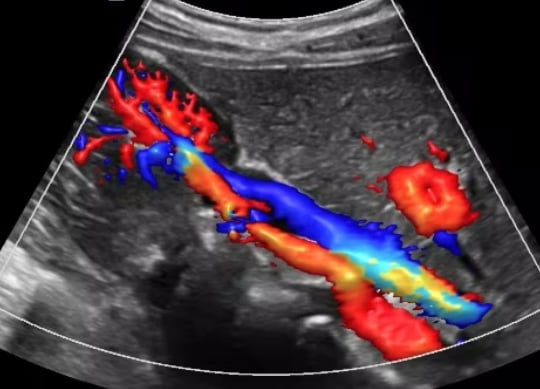

A Renal Doppler is an ultrasound routinely performed because it is a useful technique for evaluating blood flow through the renal arteries supplying the kidneys. A narrowing of these arteries is most often caused by atherosclerosis, a build up of plaque (fat and cholesterol) in the artery walls. Another significant cause is fibromuscular dysplasia (FMD), where the artery wall develops abnormally and Takayasu's arteritis where the vessel becomes inflammed.

Reduced blood flow to the kidneys can affect their ability to filter waste and excess fluid from the blood, potentially leading to kidney disease. Narrowing of the renal arteries prevents oxygen-rich blood from reaching your kidneys, potentially leading to high blood pressure, kidney damage, fluid retention, electrolyte imbalances, and an increased risk of cardiovascular events. The Doppler ultrasound can also be used to monitor the blood flow to a transplanted kidney.

We have the in-depth understanding of normal anatomy, as well as important anatomical variants, necessary for correct interpretation. The interpretation of renal Doppler examinations is challenging for those with limited experience or those unfamiliar with fundamental concepts and nomenclature. The deep location of both kidneys in the retroperitoneum with relatively small caliber renal arteries further adds to technical challenges associated with this study, and an experienced vascular sonographer is paramount.